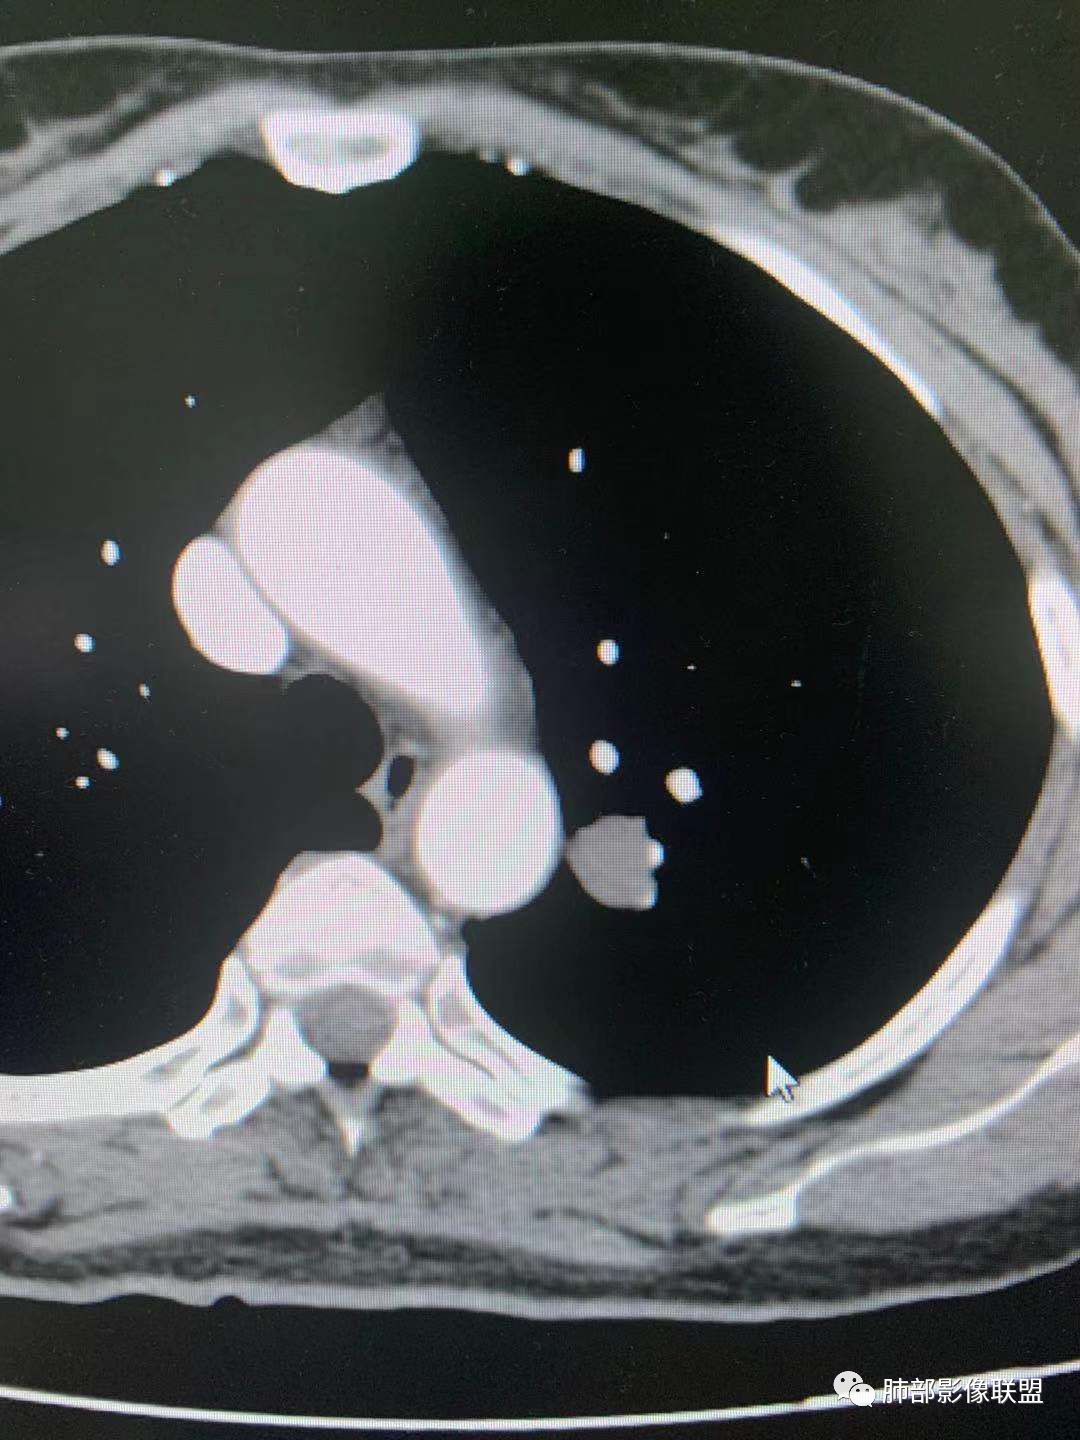

一.尖后段高密度大结节:

1.左肺上叶尖后段较大类圆形实性密度结节影,密度均匀,中等程度强化。

2.实性密度区边缘相当清楚,表面欠光整,偶见毛刺、棘突和旁出血管结构,未见典型的深分叶及邻近胸膜凹陷。

3.可疑支气管进入受阻。可惜缺乏连贯图像或冠矢状位以资判断。

4.病灶与胸膜之间有连线,邻近段支气管及肺血管整体后移,提示病灶还是有一定收缩性。

如上,单就这实性结节,硬化性肺细胞瘤(PSP)和腺癌似乎都能够解释,形态太规整了一些。

5.病灶周围见边界清楚的磨玻璃影,有点醒目,有点意外!

这是无论如何不能忽视的征象!

这点强烈提示,要么整个病灶恶性(腺癌),要么良性病灶旁滋生恶性病灶。

两年前左上肺的病灶什么位置,什么模样,是否相关?我们不得而知。